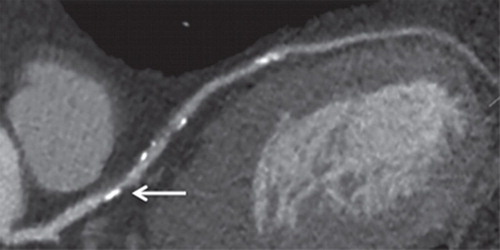

Estrategias diagnósticas para la evaluación de la sospecha de enfermedad arterial coronaria estable: revisión sistemática y metanálisis.

Para la evaluación inicial de los pacientes con sospecha de enfermedad de las arterias coronarias estable, la angiografía por tomografía computarizada coronaria se asoció con efectos para la salud similares a la remisión directa a la angiografía coronaria invasiva y con un beneficio para la salud en comparación con el ECG de ejercicio y la SPECT-MPI. Se necesita más investigación para evaluar mejor el rendimiento relativo de cada estrategia de diagnóstico.  Ann Intern Med. 6 de junio de 2023.